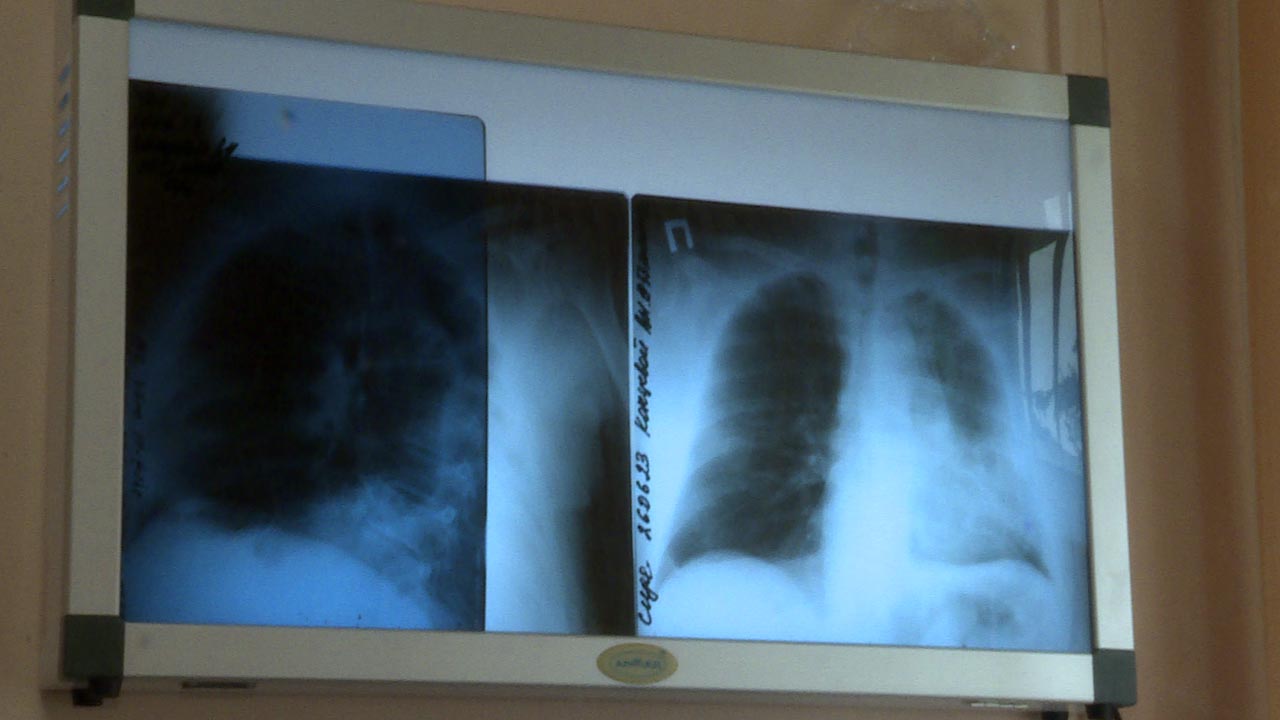

В региональном минздраве рассказали, что с 6 по 12 мая проходит Неделя сохранения здоровья легких в честь Всемирного дня по борьбе с астмой, отмечаемого 7 мая.

В связи с этим медики напомнили, что астма - это хроническое воспалительное заболевание дыхательных путей. Оно проявляется различными респираторными  симптомами: свистящими хрипами, одышкой, заложенностью в груди, кашлем.

"Для профилактики и контроля астмы важно регулярно наблюдаться у врача, соблюдать рекомендации по лечению и избегать контакта с аллергенами", - подчеркнули в калужском министерстве здравоохранения.

В числе главных факторов, мешающих нормальной работе легких, специалисты называют курение, недостаточную физическую активность и избыточный вес.